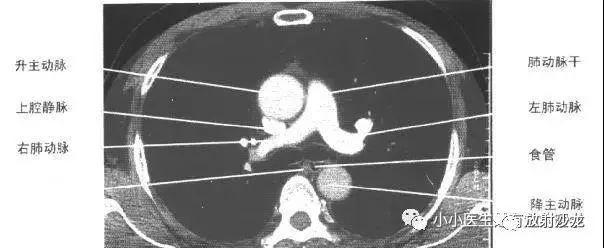

横过左 颈总动脉与头臂干的前方,向下与右头臂静脉汇合成上腔静脉

第37期(结果见18楼) ct扫描示升主动脉右后方见上腔静脉,其左后见

人字形的肺动脉,剩下的为上腔静脉.